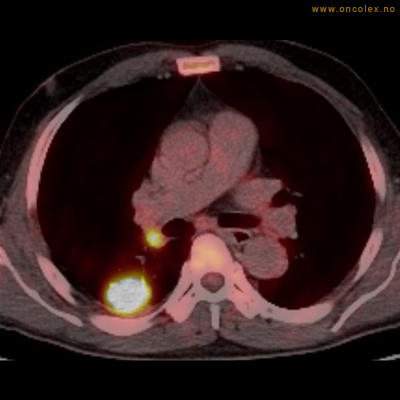

Eksempler på funn

Vev som tar opp mer radioaktivt stoff, synes som hvite områder som lyser opp mer i forhold til annet vev som tar opp mindre sukker.